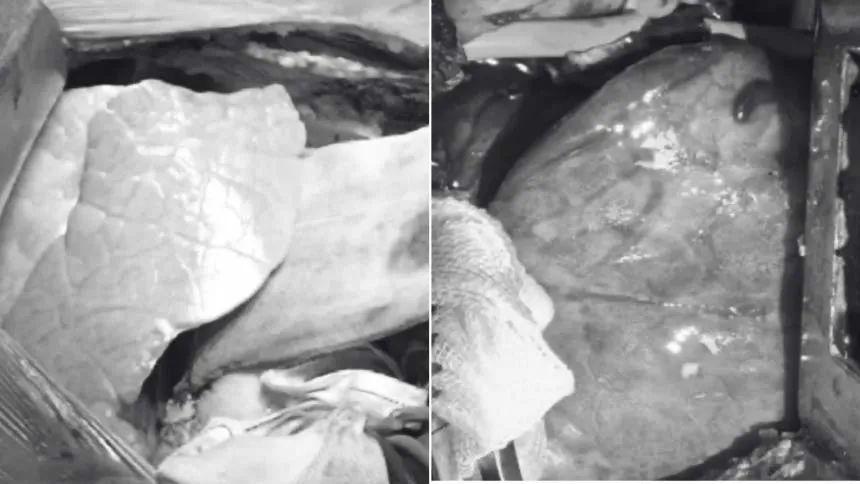

通过胸部扫描,观察到新器官充满液体——这是组织损伤的迹象,可能是由缺血再灌注损伤引起的。

上图展示了移植后的猪肺以及四天后的情况

记录显示,在为期216小时的监测期间,移植器官保持了活力和功能,期间未出现超急性排斥反应,同步病原学监测也未发现活跃感染迹象。